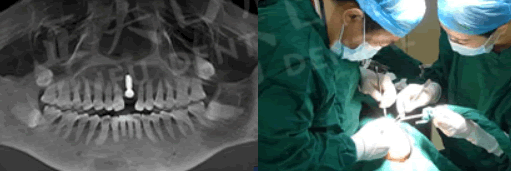

種植牙過程圖:

在種植過程中,李大媽幾乎沒有感覺到什么疼痛。